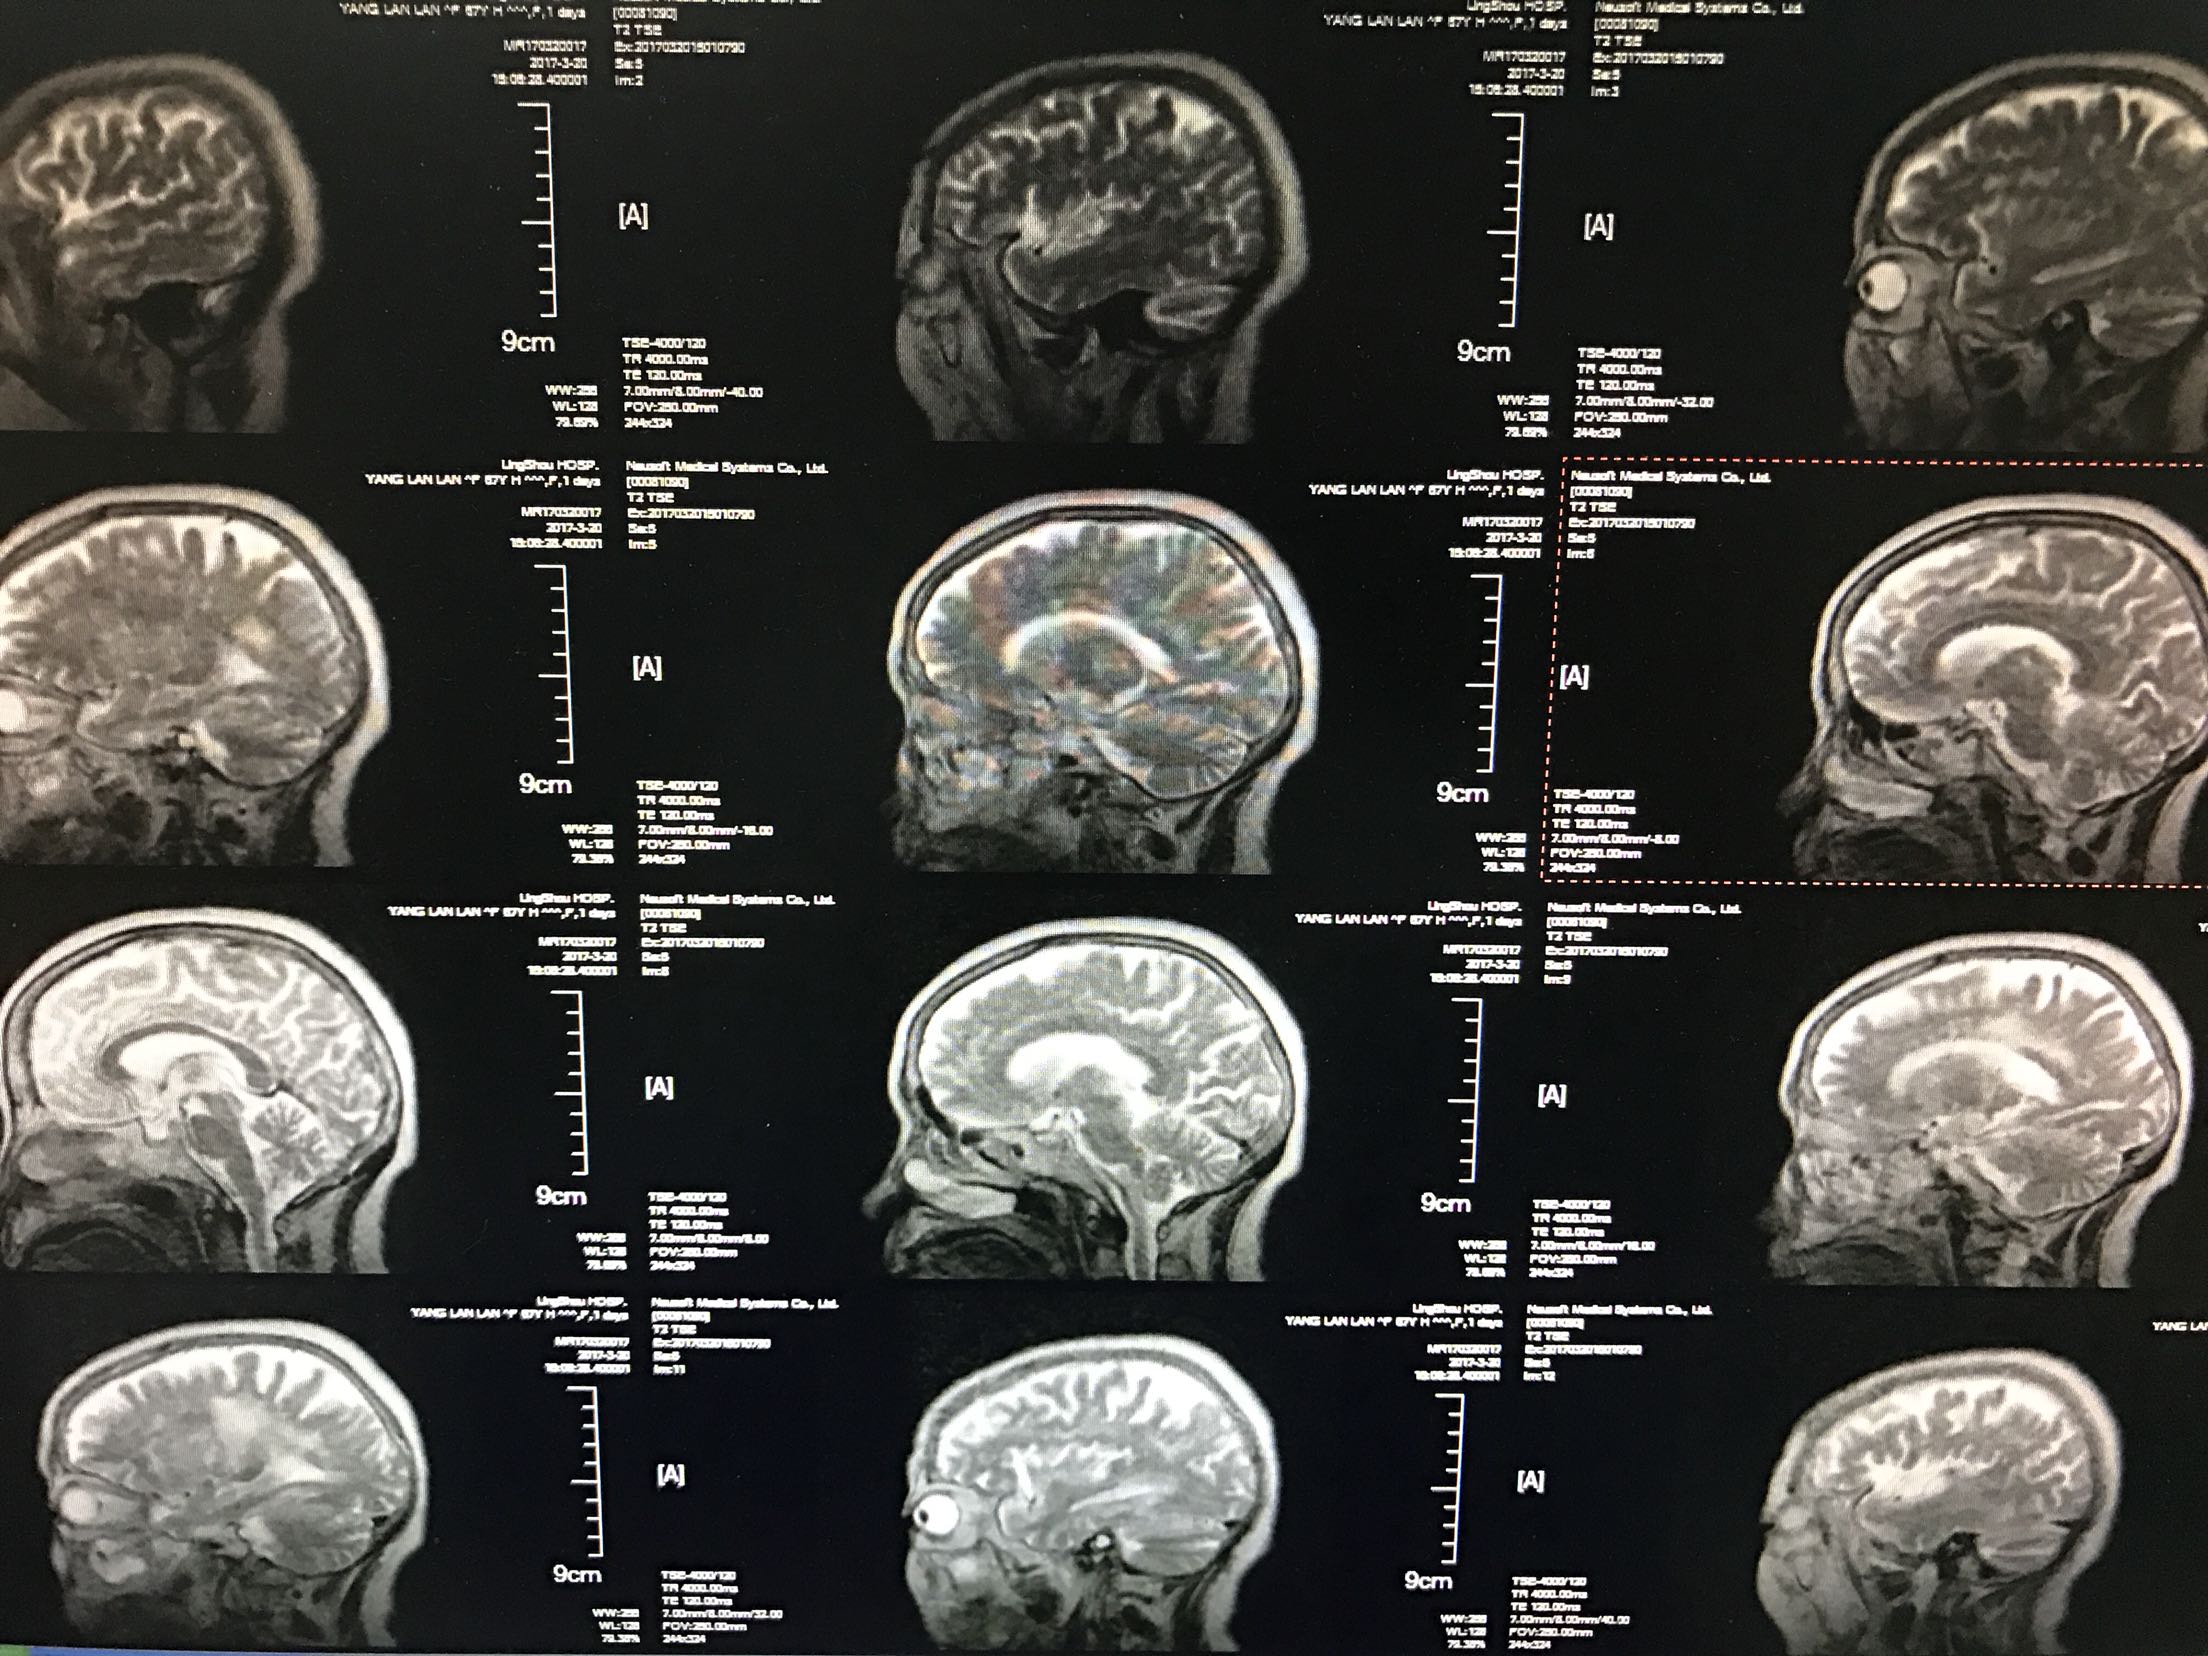

患者中年女性55岁,主因右侧肢体无力,言语不利1天入院,既往糖尿病病史5年,平素口服二甲双胍及格列吡嗪,未控制饮食,自诉血糖控制不佳,时高时低!脑出血病史4年,留有左侧肢体无力,生活尚能自理,患者缘无1天前,活动时突然出现右侧肢体无力,右上肢尚可抬起,持物不牢,右下肢不能负重,不能自行行走,同时出现言语不利,说话含糊不清,但无听理解障碍,查CT:双侧基底节,左丘脑腔梗及软化灶,测血糖18.3mmol/l,为进一步治疗收住院

体温36.9℃脉搏106次/分,呼吸20次/分,血压140/87mmhg,神情,言语欠流利,眼动充分,无水平性眼震,伸舌居中,颈无抵抗,双肺呼吸音清,未闻及干湿性啰音,心音低钝,心律规整,未闻及杂音,左侧肢体肌力2级,右侧肢体肌力4级,双巴氏征阳性,克氏征阴性,

1.脑梗死2.2型糖尿病3.脑出血后遗症期,给于抗凝,降血糖,抑制血小板聚集,稳定动脉板块等治疗